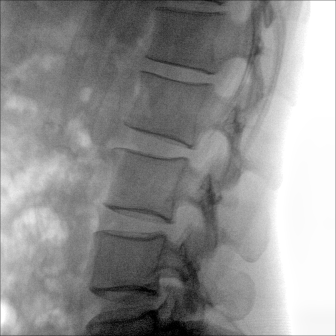

動態(tài)板C形臂 開啟清晰影像新篇章

大尺寸動態(tài)平板探測器,高DQE、低噪聲、圖像清晰。采用多分辨率圖像增強處理技術,不同部位不同圖像處理算法,滿足客戶多樣化的需求。